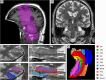

This paper for the 20th anniversary of the Alzheimer's Disease Neuroimaging Initiative (ADNI) provides an overview of magnetic resonance imaging (MRI) of medial temporal lobe (MTL) subregions in ADNI using a dedicated high-resolution T2-weighted sequence. A review of the work that supported the inclusion of this imaging modality into ADNI Phase 3 is followed by a brief description of the ADNI MTL imaging and analysis protocols and a summary of studies that have used these data. This review is supplemented by a new study that uses novel surface-based tools to characterize MTL neurodegeneration across biomarker-defined AD stages. This analysis reveals a pattern of spreading cortical thinning associated with increasing levels of tau pathology in the presence of elevated amyloid beta, with apparent epicenters in the transentorhinal region and inferior hippocampal subfields. The paper concludes with an outlook for high-resolution imaging of the MTL in ADNI Phase 4. HIGHLIGHTS: As of Phase 3, the Alzheimer's Disease Neuroimaging Initiative (ADNI) magnetic resonance imaging (MRI) protocol includes a high-resolution T2-weighted MRI scan optimized for imaging hippocampal subfields and medial temporal lobe (MTL) subregions. These scans are processed by the ADNI core to obtain automatic segmentations of MTL subregions and to derive morphologic measurements. More detailed granular examination of MTL neurodegeneration in response to disease progression is achieved by applying surface-based modeling techniques. Surface-based analysis of gray matter loss in MTL subregions reveals increasing and spatially expanding patterns of neurodegeneration with advancing stages of Alzheimer's disease (AD), as defined based on amyloid and tau positron emission tomography biomarkers in accordance with recently proposed criteria. These patterns closely align with post mortem literature on spread of pathological tau in AD, supporting the role of tau pathology in the presence of elevated levels of amyloid beta as the driver of neurodegeneration.